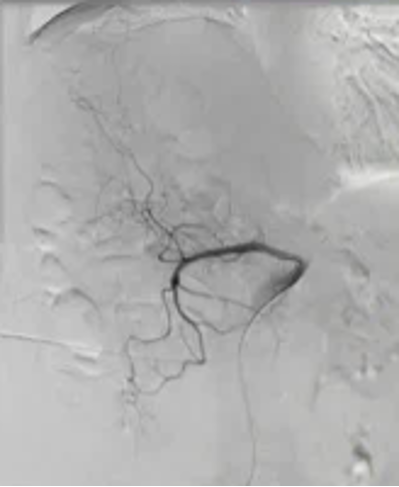

Empiric Colonic Embo Case

|

Bleeding into diverticulum

Region of bleeding tic

Post embo |